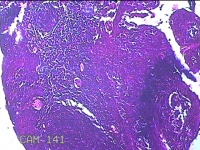

性别

女

年龄

6岁

临床诊断

1.阻塞性睡眠呼吸暂停综合征 2.腺样体肥大 3.扁桃体肥大 4.变应性鼻炎

一般病史

鼻塞、张口呼吸伴睡眠呼吸暂停半年余。

标本名称

双侧扁桃体

大体所见

灰白粉红色扁桃体4x3x0.8cm两个,表面均有部分糜烂,切面灰白粉红色,结节状,质软。